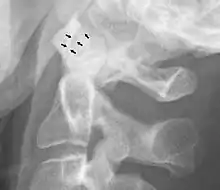

Abnormal widening

A widening of the atlanto-axial joint, as measured between the posterior surface of the anterior arch of atlas and the front of the odontoid process, indicates an injury to the transverse atlantal ligament.[5] Normally, this atlanto-dental distance is less than 2 mm, sometimes a maximum of 3 mm is accepted in men and 2.5 mm in women.[5]